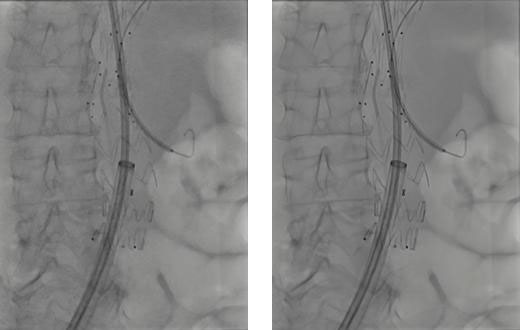

左がOPTIQ AIが無い状態の画像。右がOPTIQ AIがあるときの画像で、より鮮明な写真となっている